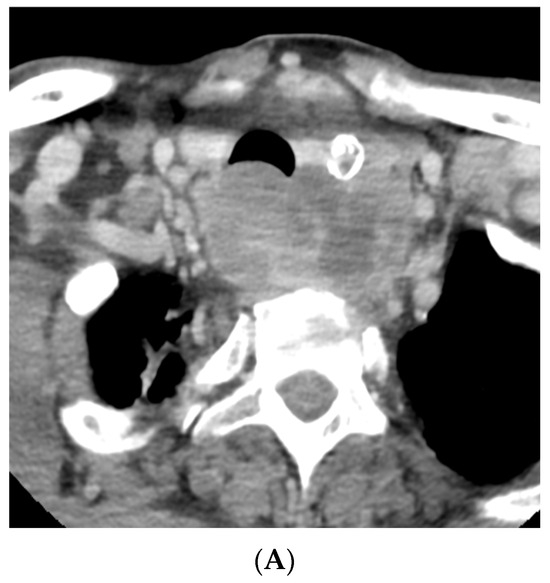

As outlined by the accompanying patient testimony, a 65-year-old gentleman presented with a 6-week history of dysphagia. Computed tomography (CT) imaging of the thorax, abdomen, and pelvis, and magnetic resonance imaging (MRI) of the neck revealed a 7.2 centimeter (cm) mass centered in the left lobe of the thyroid. The mass involved the cervical esophagus and posterior tracheal wall, leading to moderate cervical tracheal airway narrowing and invasion of both the prevertebral fascia and the posterior arch of the cricoid with metastatic right level 2, bilateral level 3, and bilateral level 4 neck nodes (shown in Figure 1 and Figure 2). A 12 millimeter (mm) right hilar node and right paratracheal and subcarinal nodes of less than 10 mm were suspicious for malignant involvement (Stage IVC) [13].

Figure 1.

Pre-treatment CT imaging demonstrated a heterogeneous mass centered in the left thyroid with enhancing, calcified, and hypo-enhancing components invading the esophagus and trachea with enhancing neck adenopathy (A,B). (A) Axial image at the level of the second thoracic vertebra. (B) Axial image at the level of the sixth cervical vertebra.